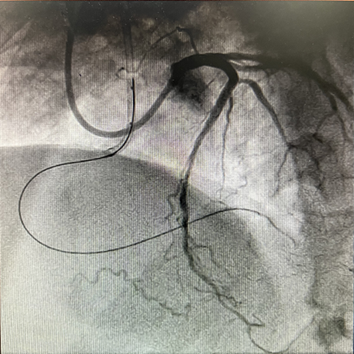

PCI过程:术中首先尝试正向开通(AWE),逐步升级导丝,均多次进入内膜下,反复尝试不能送入远端真腔,王健主任果断启动正向ADR技术,利用Corsair微导管于右冠近段制造正向夹层,使用专用器械Stingray球囊,Gaia Third导丝穿刺,

成功通过血管内膜下重新进入远端血管真腔,经过多体位投照、逆向造影均证实为真腔,顺利开通闭塞病变。

正向造影可见右冠全程弥漫狭窄病变

序贯植入4枚第二代药物洗脱支架覆盖病变。

无术中并发症,手术完美收官。